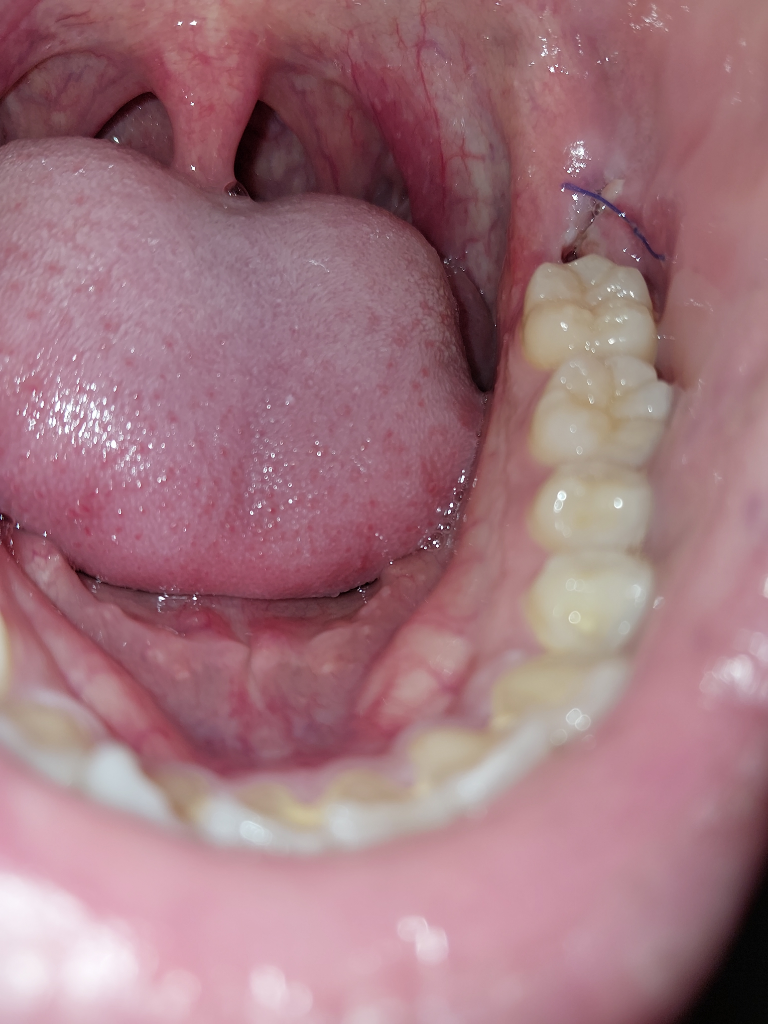

매복사랑니 발치한지 4일째인데 구멍이 조금 생겼습니다

발치한지 4일째 아침에 일어나서 잇몸상태를 보니 전날까진 보이지 않던 구멍이 보이더군요 정상적인 치유 과정인지 뭔가 잘못된건지 잘 모르겠습니다

오늘 상태

물을 마시면 아주조금 따끔거리긴 하는데 무시하고 넘어갈 정도의 통증이긴합니다 괜찮을까요?

정상적으로 잘 낫고. 있습니다. 사진 상에서, 증상을 봤을 때 특별히 걱정하실 부분은 안보입니다.

발치 부위에 이가 빠지고 구멍이 생긴것으로 보입니다. 이는 정상적인 현상이며 잇몸은 시간이 지남에 따라 차오르게 됩니다. 잇몸이 차오르는 기간은 개인마다 차이가 있으며 3-6개월 이상 시간이 소요가 됩니다.

사랑니 발치하시고 실로 매꿔놓는건 잇몸이 봉인하는게 아니라, 음식물이 더 들어가라고 해놓은겁니다. 약간 구멍이 생겨도 크게 문제가 되지 않습니다.